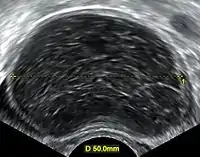

| A simple ovarian cyst of most likely follicular origin | |